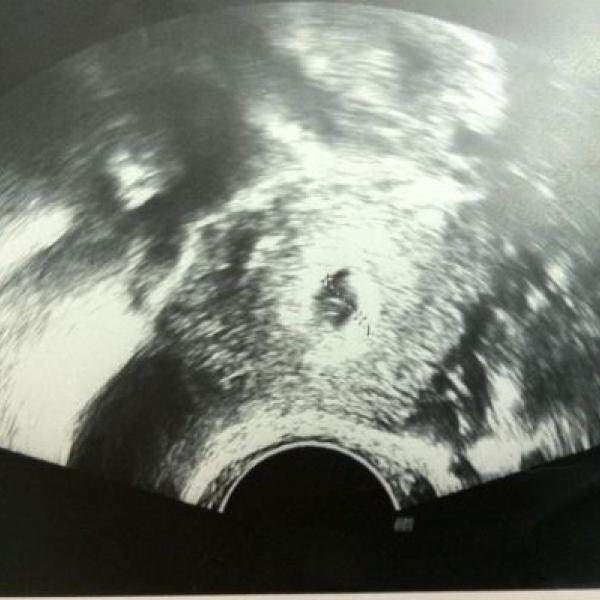

Nemůžu pochopit, proč se to kdysi povedlo takto snadno a od té doby nic. Mám za sebou laparoskopii, při které mi zjistili 1. stupeň endometriozy na pobřišnici, tak jestli ta za to může ... nevím.